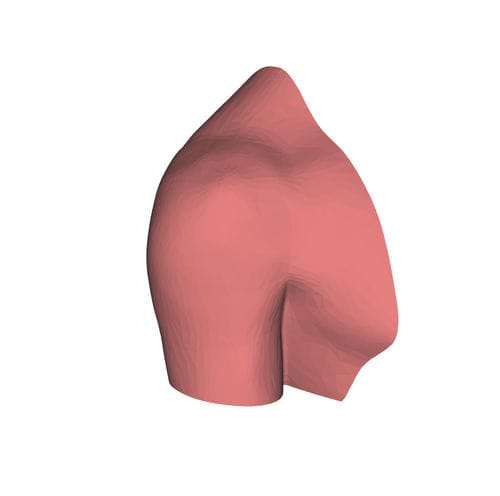

Anatomisches Modell / Schulter HUM-Efür Punktionenfür Injektionenfür Ultraschalluntersuchungen

- Körperteil

- Schulter

- Verfahren

- Ausbildung, für Injektionen, für Punktionen, für Ultraschalluntersuchungen, für interventionelles Röntgen

- Farbe

- rosa

Echogene und röntgendichte anatomische Schaufensterpuppen

für eine bessere Ausbildung in interventionellen Verfahren unter Ultraschall und Röntgenstrahlen

Identifizierung anatomischer Orientierungspunkte mit Ultraschall und Röntgenstrahlen

Training für Punktion und Infiltration unter Ultraschall und Röntgenstrahlen

Hautgetreues Stichempfinden mittels Echo und Radio

Alle unsere Schaufensterpuppen sind echogen und röntgendicht und können bis zu 600 Injektionen pro Stelle tragen.